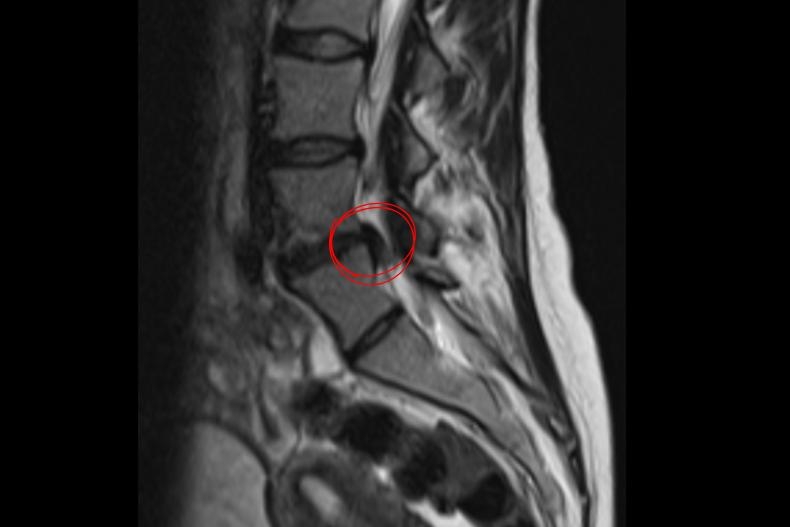

Lumbar Disc Herniation Surgery: Treating the Patient, Not the Image

Lumbar disc herniation is one of the most common conditions encountered in brain and spine surgery. Although advances in magnetic resonance imaging have increased diagnostic sensitivity, it is well known that not every radiological finding constitutes a surgical indication. Accurate treatment decisions require a combined evaluation of clinical findings and imaging results.

Within the framework of the Less Is One approach:

- Surgical intervention is planned only in the presence of significant neurological deficit or pain refractory to conservative treatment.

- Targeted surgical techniques are preferred instead of extensive and unnecessary decompressions.

- Preservation of normal anatomical structures is prioritized; therefore, instrumentation (screws and rods) is applied only when clearly indicated, and minimally invasive, muscle-sparing surgical techniques are favored.

This approach reduces surgery-related tissue damage, accelerates postoperative recovery, and improves long-term functional outcomes.